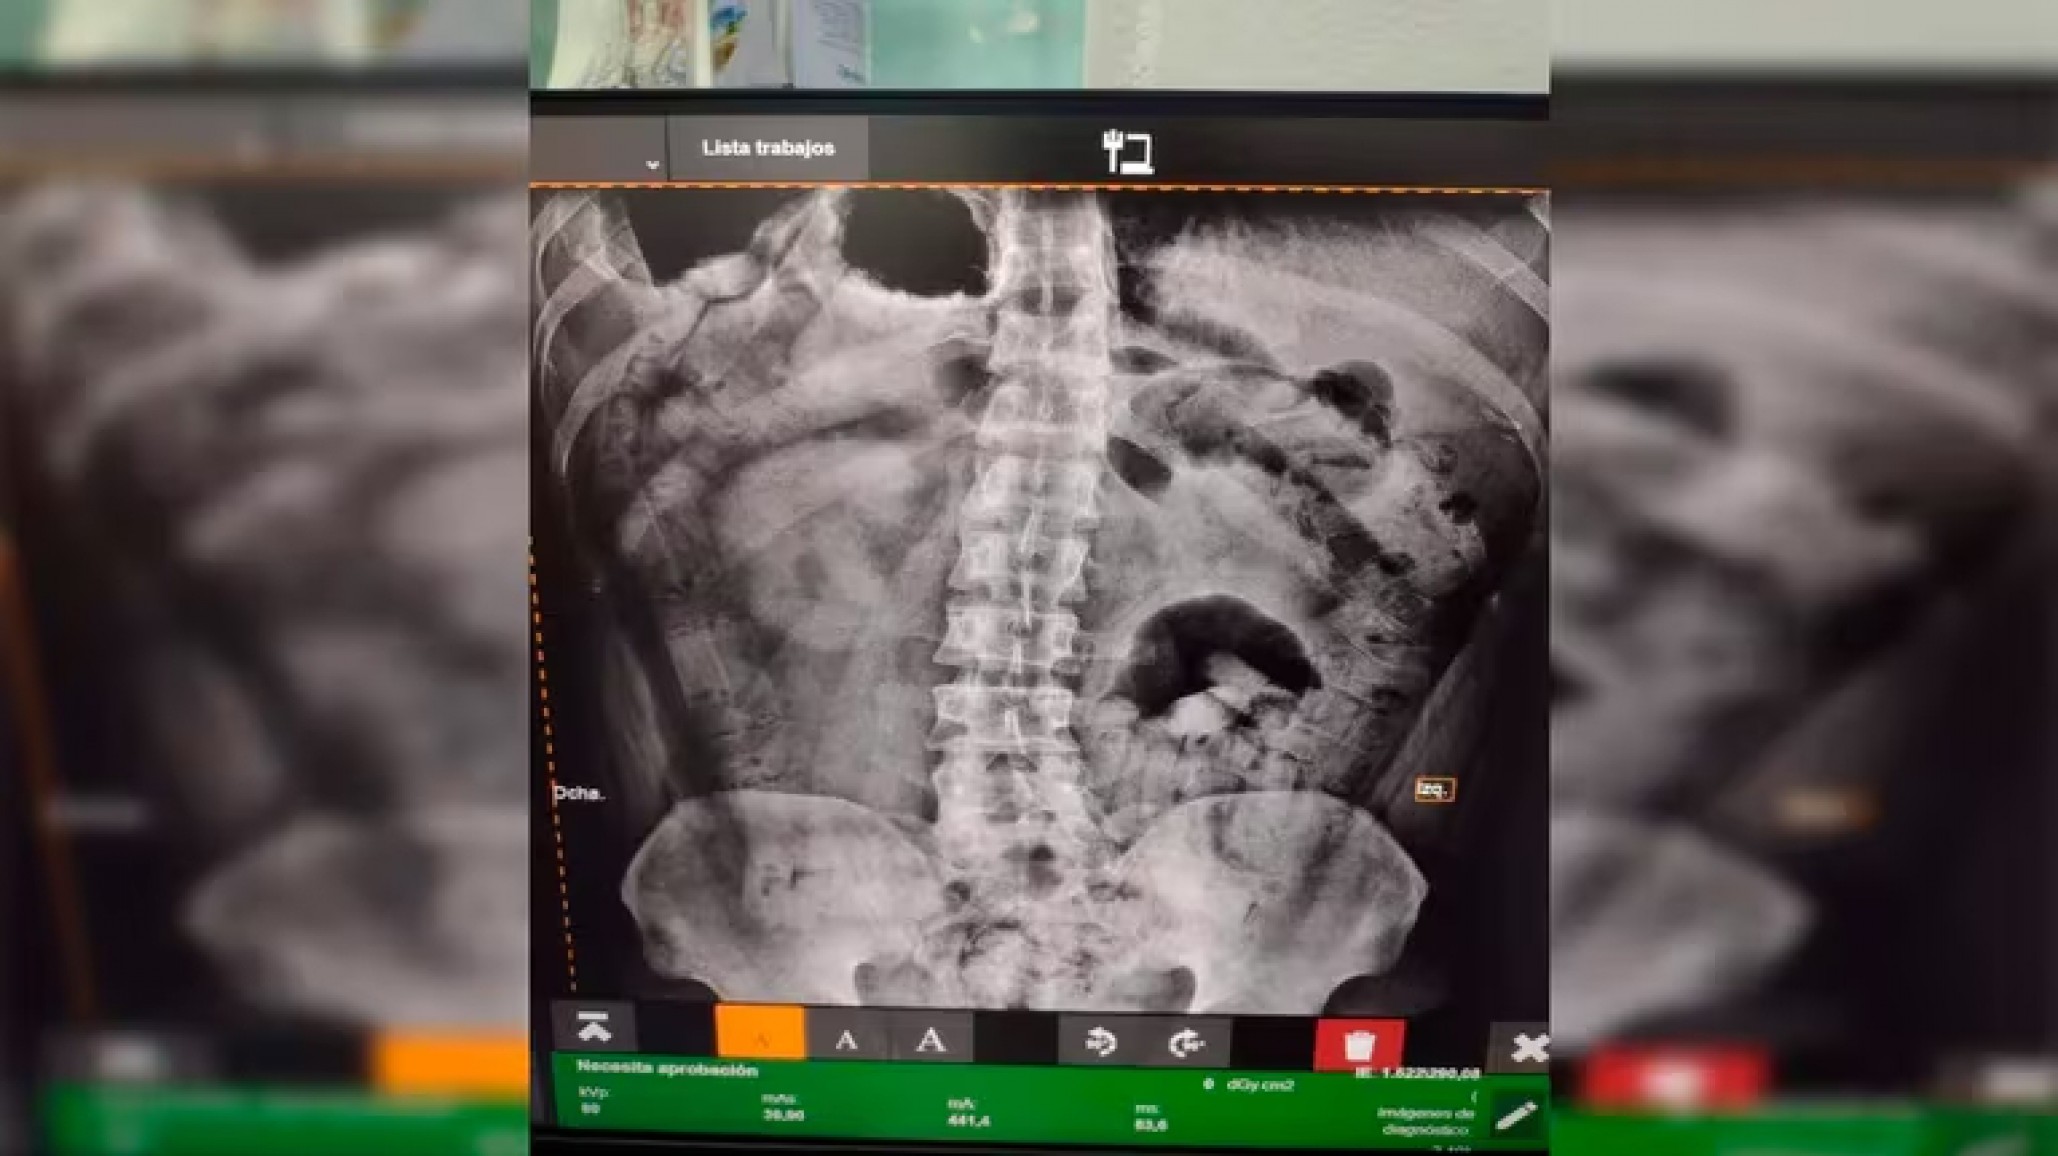

El Juzgado Federal de Tucumán ordenó trasladar a los sospechosos a un centro de salud, donde se les realizaron pruebas de rayos X, revelando la presencia de cuerpos extraños en sus estómagos. Bajo supervisión médica, ambos expulsaron 206 cápsulas que contenían aproximadamente 2 kg de cocaína. Los dos hombres fueron detenidos por orden del Juzgado Federal de Tucumán.